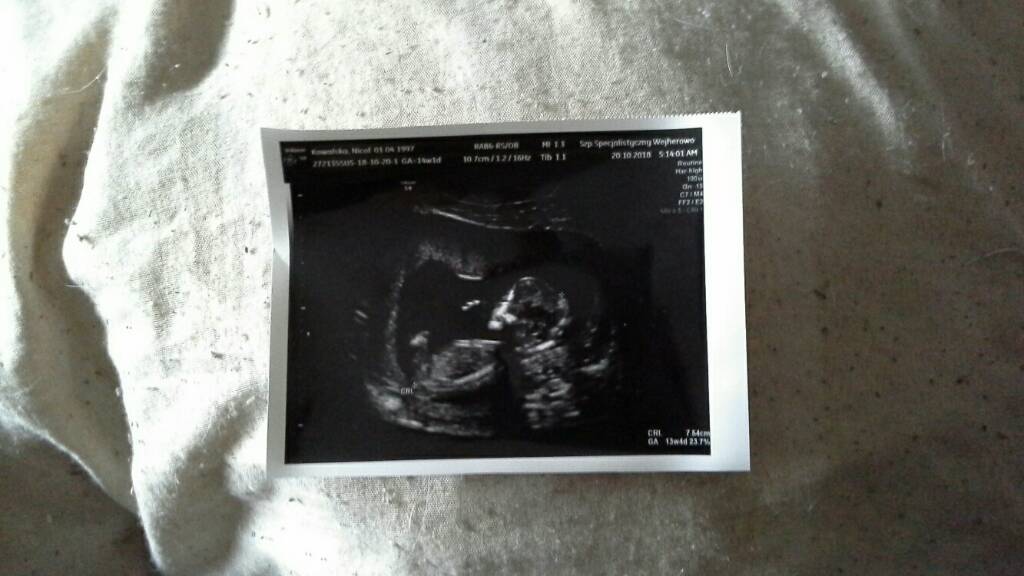

@Malaga00 super ze na Usg wszystko ok z córeczka. Odpoczywaj i wyznacz sobie w zyciu co jest wazne a co nie. Nie przejmuj sie i nie zaprzataj sobie glowy rodzina od strony partnera. Patrz tylko na siebie i dziecko.